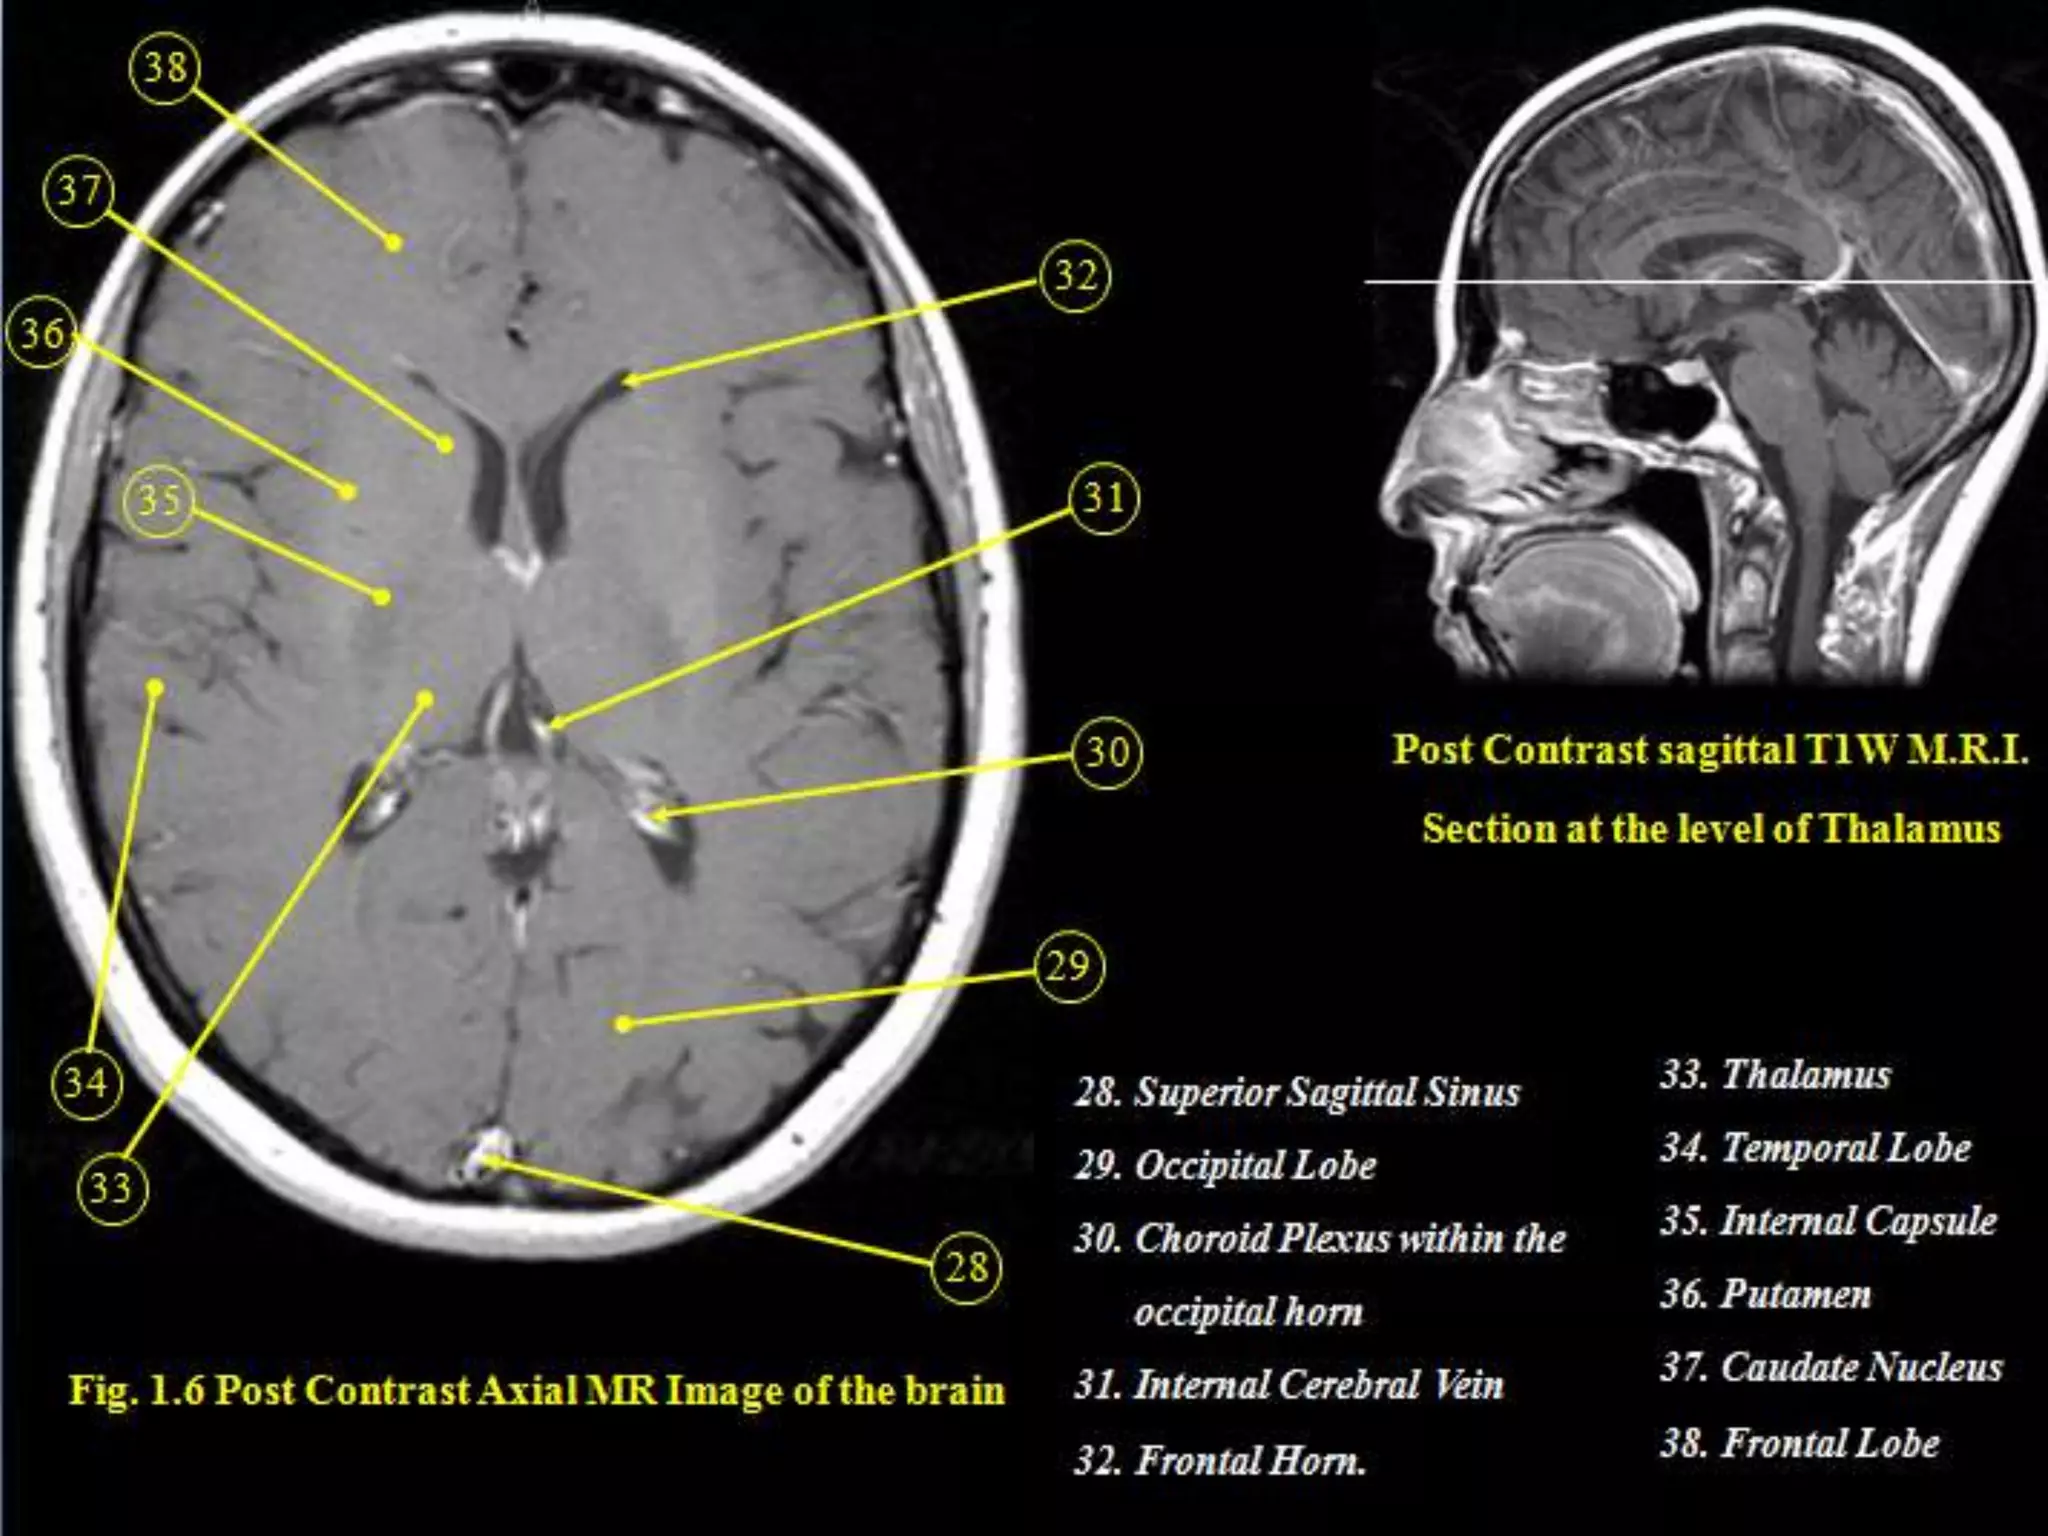

Sectional Anatomy: NormalAxial CT and MRI Anatomy. On CT and MR scans, the brain has been briefly viewed in infratentorial and supratentorial sections, as described below. CT scans are performed with a 15- to 20-degree angulation to the canthomeatal line at 8-mm increments. MRI scans are generally obtained parallel to the AC-PC line in the axial plane with 6-mm slice thickness. Using the sagittal view, the coronal sections are acquired parallel to the brain stem, and the sagittal sections are obtained perpendicular to the axial section. On MRI studies, cranial nerves IX and X can be demonstrated at this level because they emerge from the postolivary sulcus. The posterior aspect of the cerebellar hemispheres is outlined by the inferior portion of the cisterna magna.